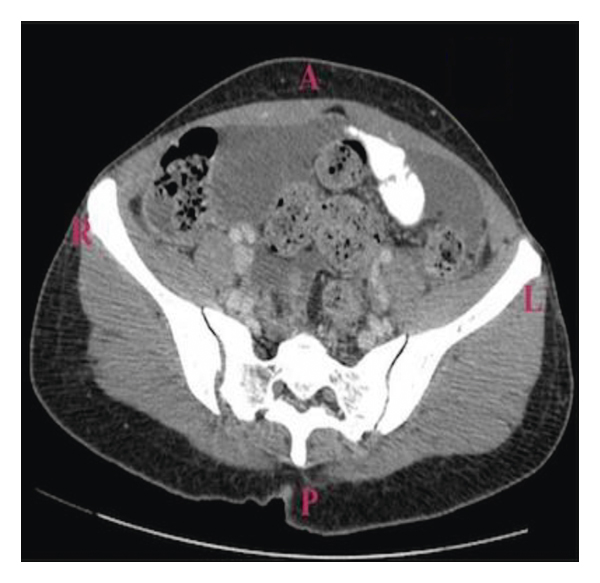

A 38-year-old Liberian female with a 12-week gestation presented to the emergency department with a 3-week history of low-grade subjective fever, night sweats, unintentional weight loss, gradually worsening abdominal pain, and intermittent spotting. Vital signs were stable on presentation, physical exam noticeable for gravida abdomen, otherwise unremarkable. Laboratory examination revealed beta hCG 118471, which was otherwise unremarkable. Pelvic ultrasound confirmed a 12-week viable intrauterine pregnancy. The patient was admitted to the hospital for close monitoring. Hospital course was complicated by massive pleural effusion, low-grade fever, progressive worsening abdominal pain, and spontaneous abortion. Non-contrast-enhanced computed tomography of the chest (Figure 1) revealed large right-sided pleural effusion, and contrast-enhanced computed tomography of the abdomen and pelvis (Figure 2) revealed bilateral hilar adenopathy, ascites, thickening and enhancement of the peritoneum, and mottled nodular-appearing soft tissue consistent with omental caking suspicious for peritoneal carcinomatosis. She underwent extensive workup including surgical and oncologist consultations for possible exploratory laparotomy and discussion of treatment options for presumed ovarian neoplasm. Blood work revealed elevated carbohydrate antigen (CA) 125 and positive QuantiFERON-TB Gold, but adenosine deaminase, CA 19, alpha-fetoprotein, and inhibin B were within normal limits. Diagnostic laparoscopy with biopsy revealed significant pelvis ascites and diffuse miliary lesions throughout the peritoneum. She underwent dilatation and curettage; histopathologic examination showed chronic granulomatous inflammation with no evidence of neoplasm. Special stains on tissue sections and ascitic fluid stain revealed rare acid-fast bacilli, suggestive of mycobacterial granulomatous peritonitis. Additional questioning indicated a history of positive PPD skin test a year prior without follow-up treatment. The patient was placed on four-drug anti-tuberculous therapy and had a complete recovery.